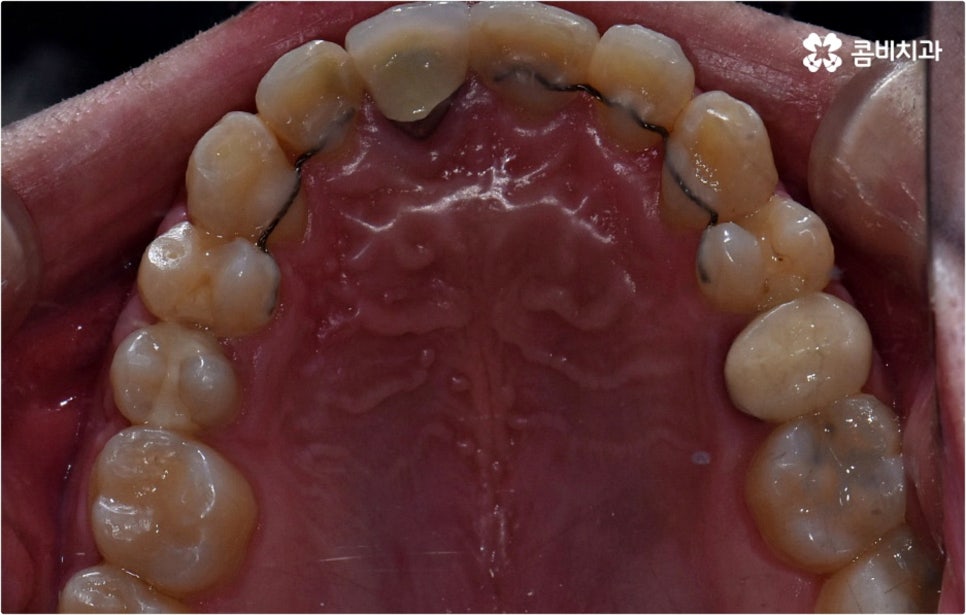

출처 아카이브 열기웃을 때 살짝 드러나는 덧니는 사람에 따라 매력 포인트로 느껴지는 경우도 있지만 구강 건강 측면에서 보면 치아와 치아가 겹쳐진 부분에 음식물 찌꺼기가 남아 치석이 쌓이기 쉽기 때문에 충치나 잇몸병이 더 자주 발생할 수 있으므로 주의하실 필요가 있습니다. 이와 같이 덧니는 옆 치아와 잇몸에까지 지속적으로 좋지 않은 영향을 주기 때문에 개선해 주는 게 좋은데요, 특히 덧니의 개수가 많아 삐뚤빼뚤한 정도가 심하다면 교합이 잘 맞지 않아 씹기가 불편하거나 턱관절 압박, 통증 등을 유발할 수 있으며 나아가 안면비대칭으로 이어질 수 있기 때문에 방치하지 말고 될 수 있는대로 빨리 덧니교정 을 통해 이를 바로잡아 주시길 권유드리고 있습니다.

덧니교정 시 환자분들의 상황에 따라 치아 이동에 필요한 공간이 부족하지 않다면 비발치 교정이 가능한데요, 이런 경우 치아 사이를 살짝 갈아서 여유 공간을 만드는 치간 삭제 방법, 마지막 어금니를 후방으로 이동시키는 방법, 그리고 악궁 확장 장치를 사용해 치아 사이를 벌려주는 방법 등 다양한 방법으로 공간을 만들어 치열을 가지런하게 바로잡아 줄 수 있습니다. 이때 환자분들의 구강 상태, 즉 악궁 크기 대비 치아의 크기, 치아가 겹친 정도, 덧니의 위치와 개수 등을 자세하게 검진한 다음 치아가 이동할 충분한 공간이 확보되지 않는다면 발치 교정을 하게 될 거예요.

또한 교정 치료는 사후 관리도 굉장히 중요하기 때문에 치과에서 정해준 시간 만큼 유지 장치를 잘 착용하지 않으면 치아가 원래 자리로 돌아가서 부정교합이 다시 생길 수도 있고 검진이나 스케일링 등 구강 관리에 부주의하면 주변 잇몸이 약해지면서 치주 질환이 생기기 쉬우니 이런 점들에 주의하시고 시기에 맞춰 내원하셔서 치과 케어 시스템의 도움을 받으시길 권유드리고 있습니다.